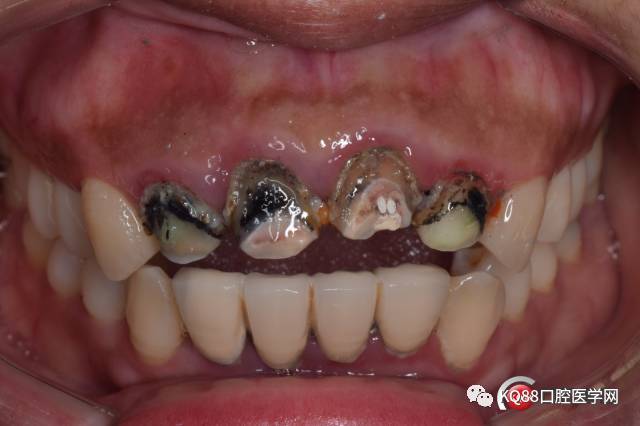

患者 女 因门牙牙龈出血,瘘管间断性溢脓5+年就诊

初诊检查:前牙烤瓷连冠修复,牙龈肿胀, A2根尖瘘管,自诉已经五年了。

初诊照片: